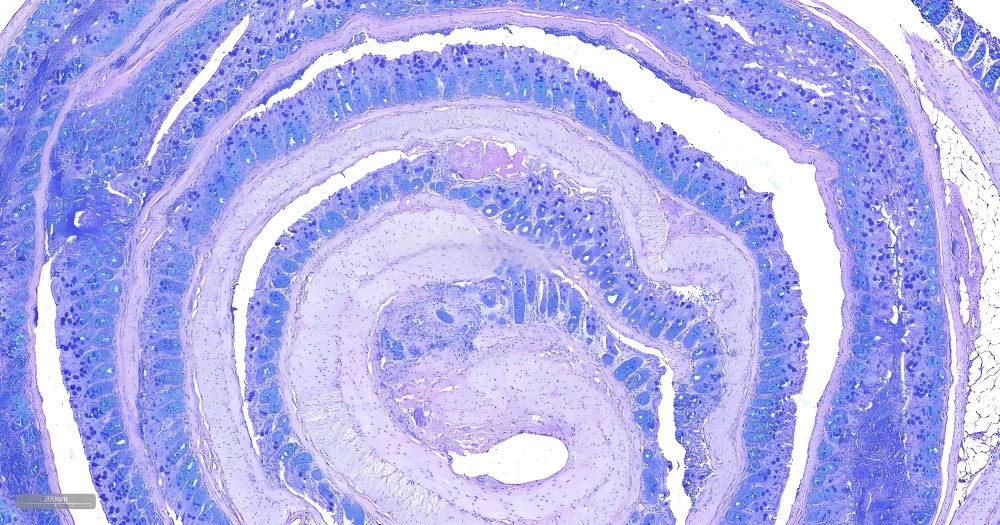

AB-PAS(阿尔新蓝-过碘酸雪夫)染色是一种组织化学联合染色技术,通过阿尔新蓝(Alcian Blue)特异性标记酸性粘多糖(如硫酸化粘蛋白),并利用PAS(Periodic Acid-Schiff)反应检测中性粘液物质(如糖原、糖蛋白),实现在同一张切片上区分两类重要碳水化合物成分。该技术具有高对比度(酸性粘液呈蓝色,中性粘液呈紫红色)和病理诊断价值,广泛应用于胃肠道杯状细胞分型、呼吸道粘液分泌评估及肿瘤微环境研究,尤其对黏液性肿瘤(如卵巢黏液性癌)的鉴别诊断至关重要。

酸性粘液物质:蓝色。

中性粘液物质和糖原:红色或紫红色。

细胞核:蓝色(苏木素复染)或红色(核固红复染)。